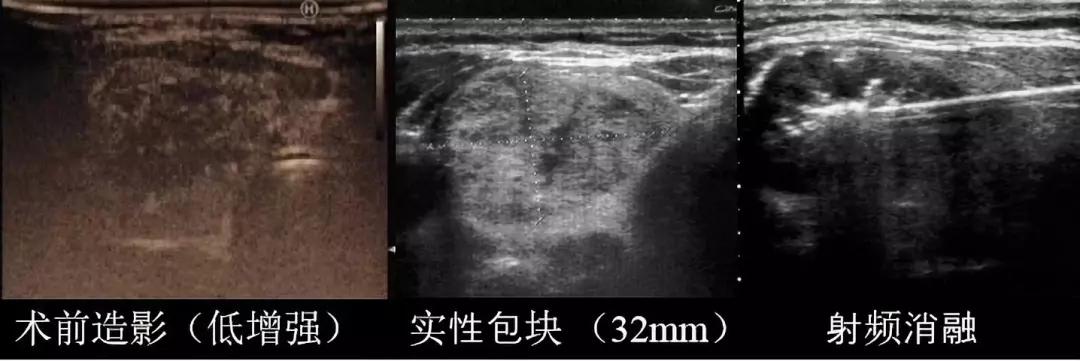

结节消融术前及术中情况

(术前造影结节呈低增强,说明结节内有血流,血流会提供“营养”,使结节生长)

消融术后病灶“吸收”情况

(术后即刻行超声造影显示“黑洞”样,表明无活性残留,结束治疗)